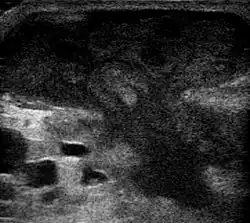

Метод выбора лечения абсцесса брюшной полости — чрескожное дренирование или пункция под контролем УЗИ.

- ↑ UOTW #66 — Ultrasound of the Week. Ultrasound of the Week (7 января 2016). Дата обращения: 27 мая 2017. Архивировано 2 ноября 2016 года.